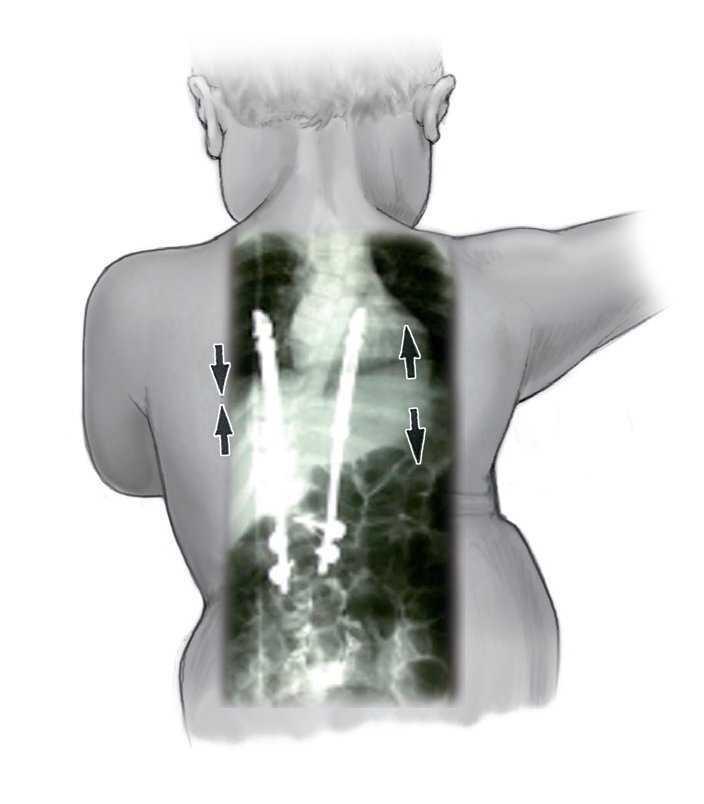

Figura 17. En el lado cóncavo se realiza la distracción, y en el lado convexo se mantiene el implante bajo compresión.

La indicación para la intervención fue en 16 casos una escoliosis congénita (figs. 24a-24c), en once casos una escoliosis neurológica y en doce casos una EIP. Las curvas se determinaron según Cobb. El ángulo de Cobb antes de la intervención medía un promedio de 65º (45-130º), y después de la intervención, un promedio de 32º (25-75º). En 18 pacientes tratamos una escoliosis torácica, en 18 pacientes una toracolumbar y en tres pacientes una lumbar (mielomeningocele). En 18 casos se utilizó un implante «costilla a costilla», en cinco casos un sistema de barra doble hasta la pelvis y en 18 casos un sistema híbrido (figs. 25 y 26).

Figuras 25a a 25c. a) Radiografía preoperatoria en proyección anteroposterior de una EIP con un ángulo de Cobb de 86º. b) Radiografía postoperatoria de una instrumentación «costilla a CL» realizada en una escoliosis toracolumbar progresiva. c) Radiografía postoperatoria en proyección anteroposterior después de 5 años. La curva se mantiene flexible y con buena corrección.